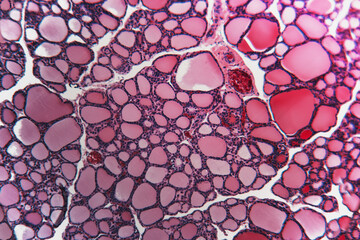

Adiponectin Glycopeptides Synthesis and its Potential for Metabolic Diseases

Fecal Microbial Biomarkers for Non-Alcoholic Fatty Liver Disease

Novel Biomaterial with Ultra High Content of GAG